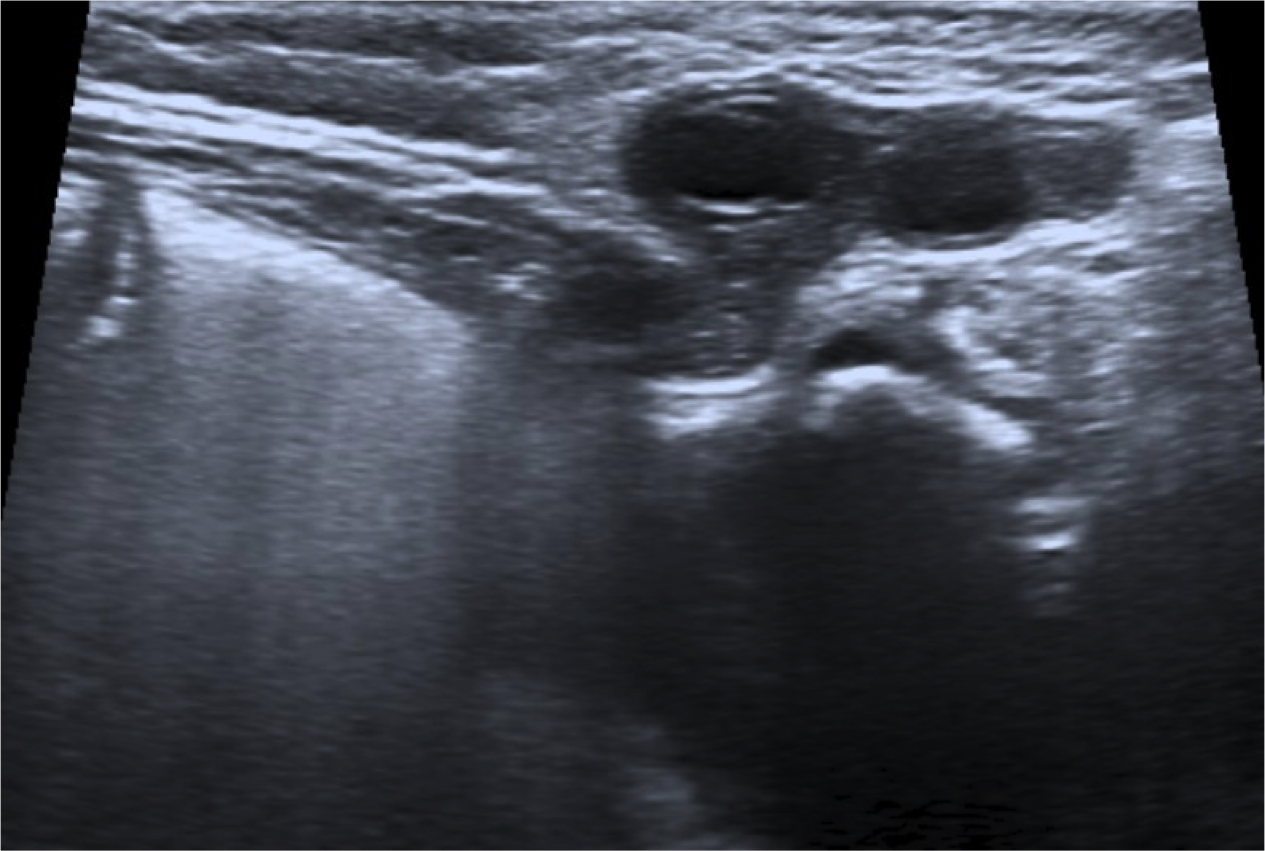

- El ovario se identifica como una masa con quistes periféricos que representan los folículos.

Como ya comentamos, el diagnóstico precoz es importante para evitar que la hernia se complique. Si la torsión del ovario se produce, el compromiso primero venos y linfático y luego arterial produciran a los signos de inflamación , congestión y finalmente isquemia. Los pacientes pueden presentar clínica y signos de irritabilidad, dolor, vómitos, gangrena y necrosis tisular. La imágen ecográfica de torsión ovárica es la de un ovario agrandado con quístes, ecogenicidad heterogénea, sin captación de flujo Doppler color y repercusión de la grasa adyacente.